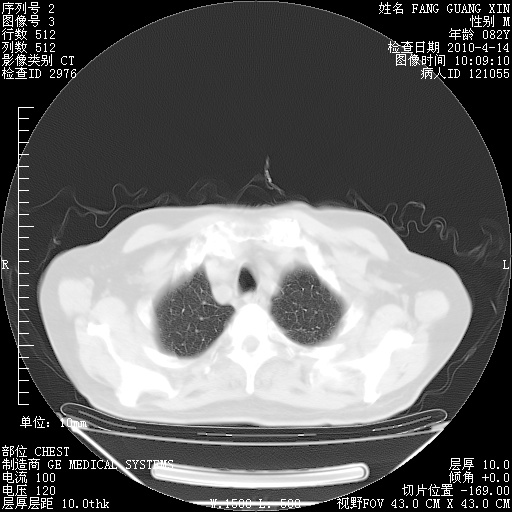

4月14日肺部CT

肺部CT平扫未见异常。